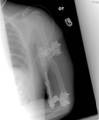

17 year old boy injured left elbow after a fall.

Pre Op

Sustained a comminuted distal fracture hmerus with shaft extension